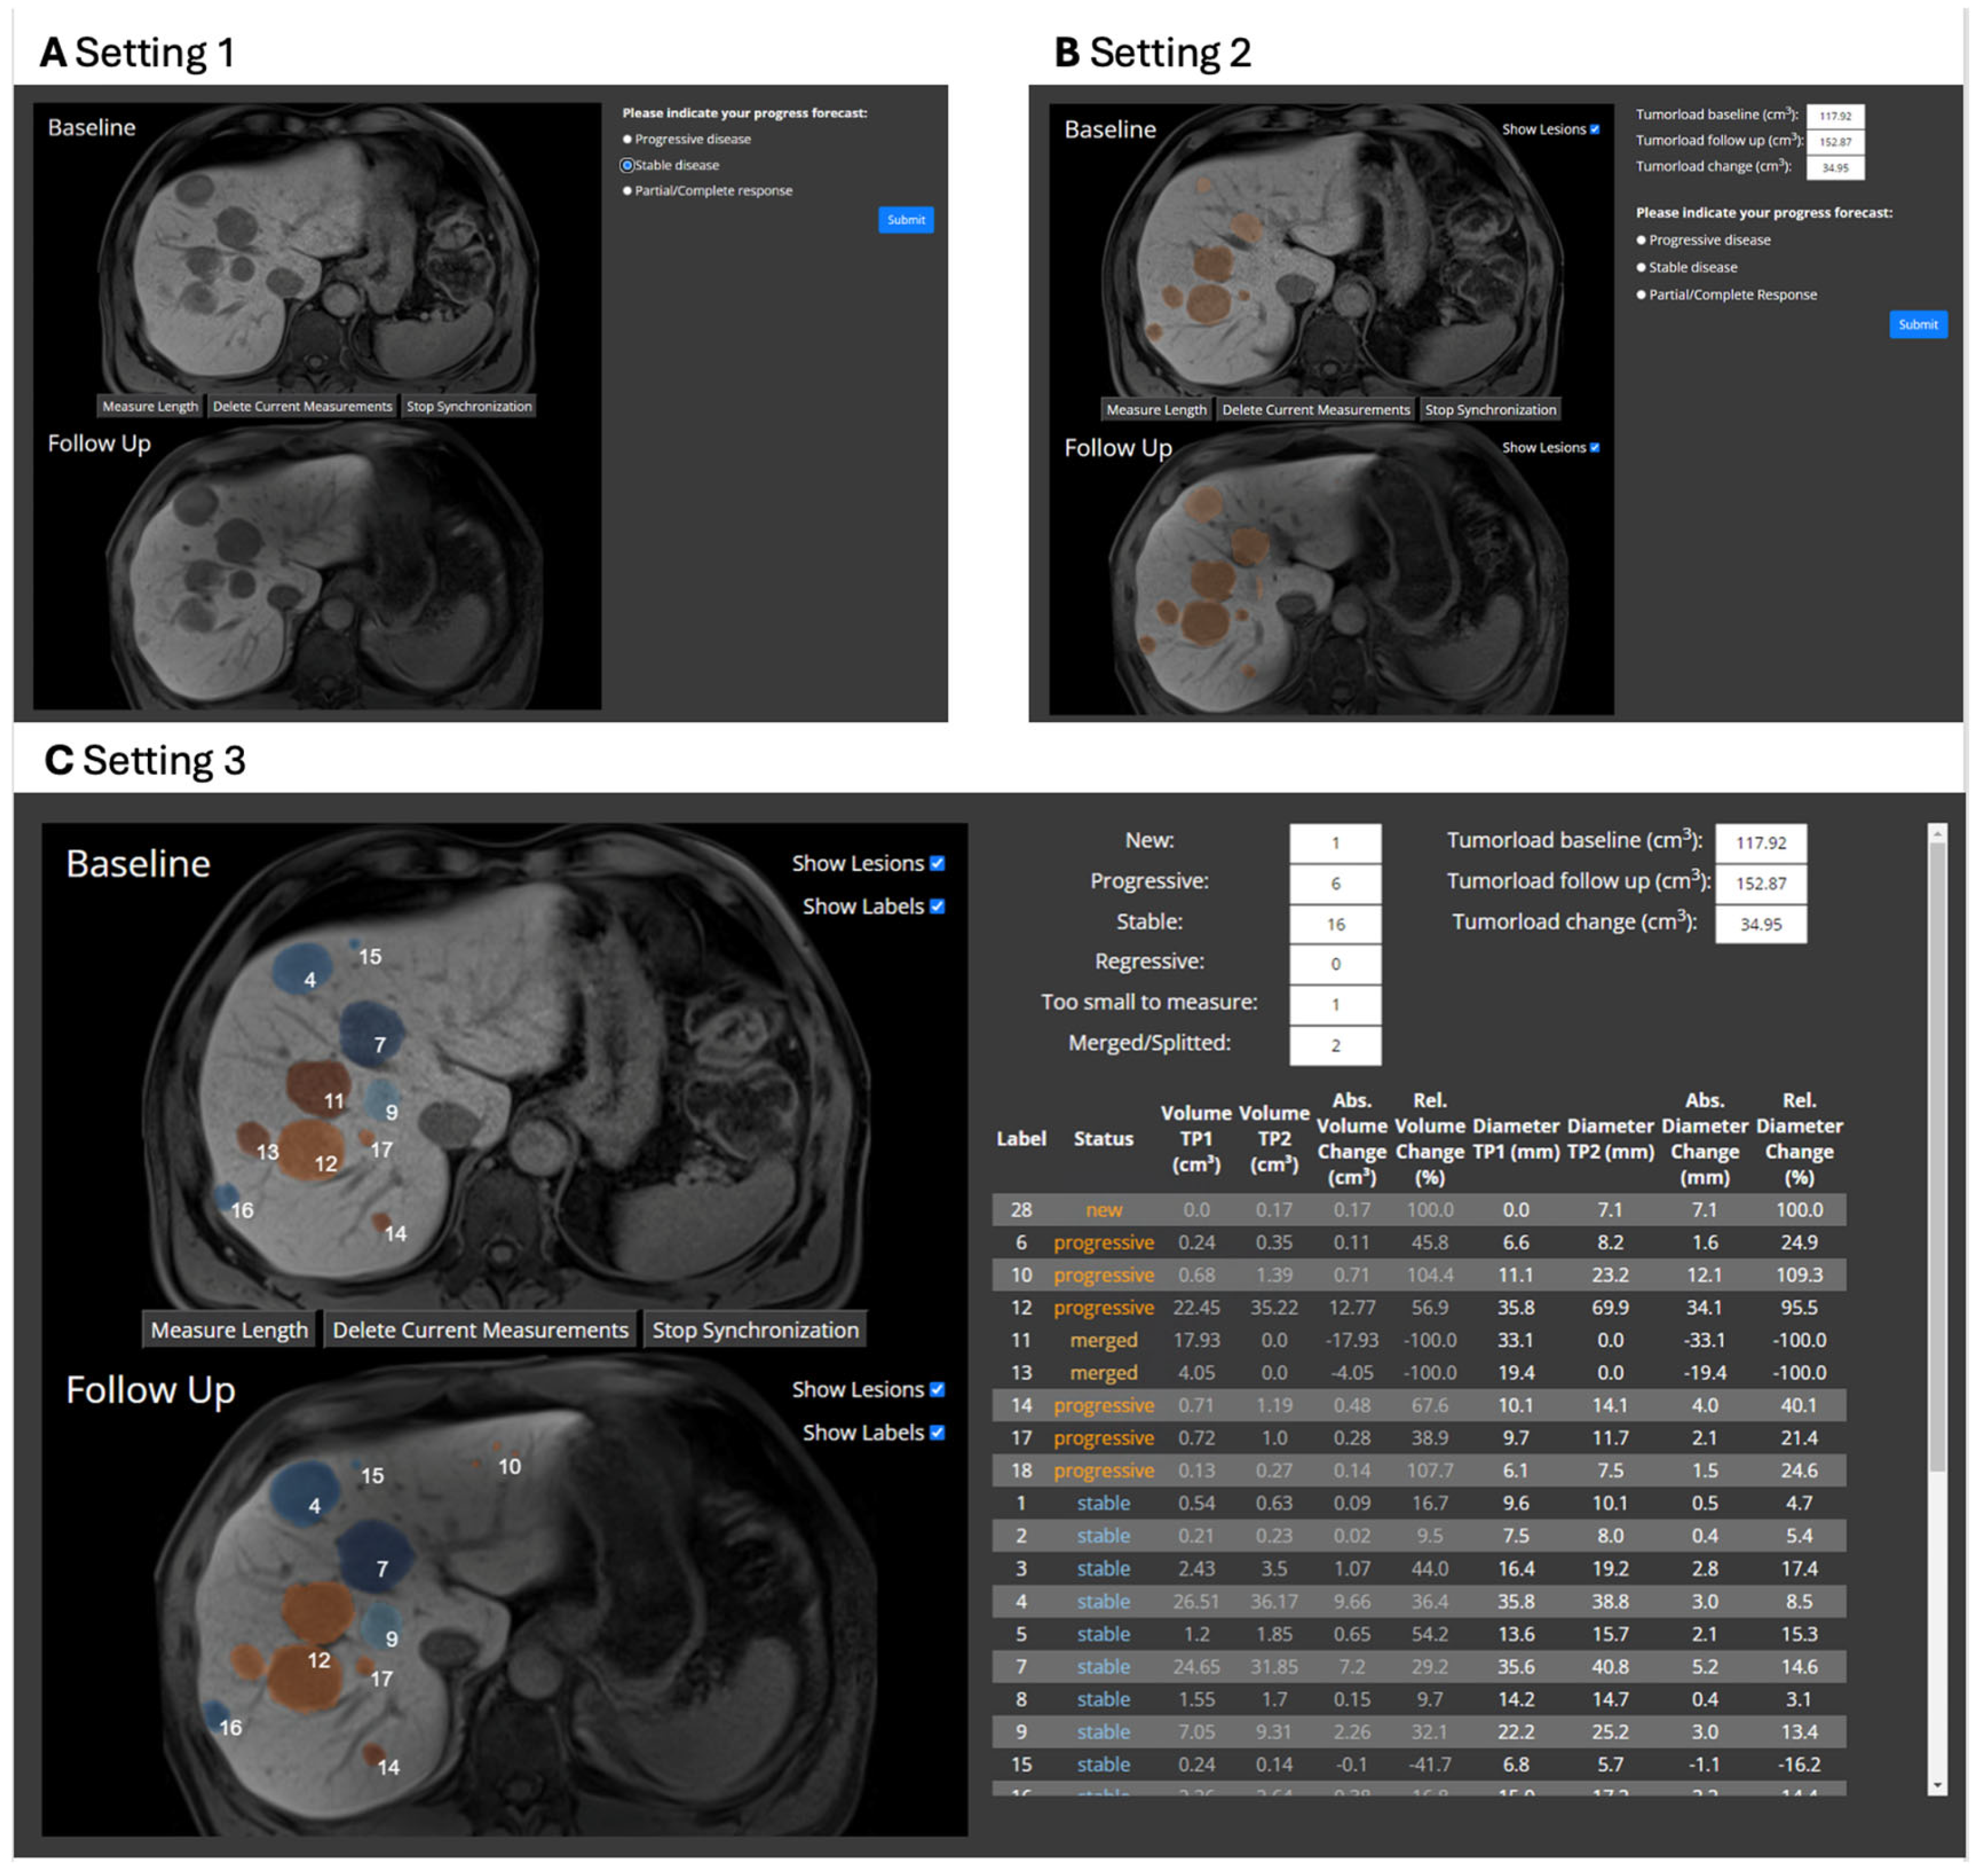

2.3. Evaluation Study

| Metric | Setting 1 | Setting 2 | Setting 3 | p-Value |

|---|---|---|---|---|

| Median decision time in s (IQR) | 13.8 (9.2–21.8) | 14.4 (10.3–24.0) | 23.8 (14.2–42.8) | <0.001 |

| Accuracy in % (SD, range) | 88.7 (SD 11.0, range 67–97) | 90.6 (SD 8.7, range 73–97) | 90.1 (SD 6.1, range 80–97) | 0.72 |

| Precision in % (SD, range) | 81.6 (SD 9.5, range 63–89) | 83.6 (SD 6.4, range 72–89) | 83.4 (SD 5.8, range 73–89) | 0.72 |

| Recall in % (SD, range) | 91.9 (SD 8.7, range 74–98) | 92.9 (SD 7.2, range 78–98) | 90.7 (SD 9.4, range 71–98) | 0.30 |